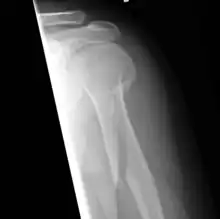

Spiral fracture

A spiral fracture (a.k.a. torsion fracture) is a bone fracture occurring when torque (a rotating force) is applied along the axis of a bone.[1] Spiral fractures often occur when the body is in motion while one extremity is planted. For example, a spiral fracture of the tibia (the shinbone) can occur in young children when they fall short on an extended leg while jumping. This occurrence is known as "toddler's fracture". Spiral fractures are also recognized as being suspicious in very young children since to obtain a fracture of this sort requires forceful twisting or jerking of the limbs. Child abuse (physical abuse) and certain conditions such as osteogenesis imperfecta (OI) are considered differentials when identifying spiral or torsion fractures.[2]